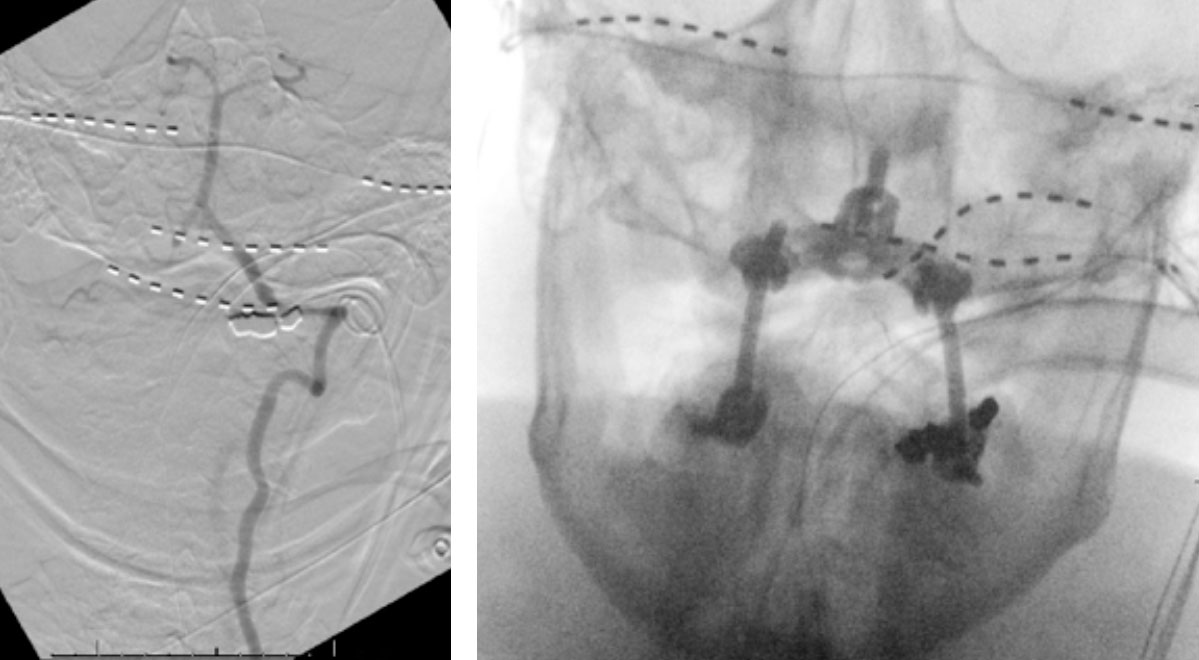

On rotation to the left, the patient experienced mild symptoms, however no significant Vertebral Artery or basilar reduction in flow was observed. On rotation to the right, the patient experiences slightly more moderate symptoms, however no significant Vertebral Artery or vascular reduction flow was observed. On hyper extension of approximately 10-15 degrees, passively performed by the patient until symptoms are reproduced, angiogram demonstrates complete occlusion of the right Vertebral Artery at approximately the C2-C1 level. (Figure 5)

It is unclear whether there is a specific bony osteophyte or soft tissue mass that is resulting in the compression. Live fluoroscopy within the neutral and extension position does demonstrate extensive arthritis and hypertrophic changes within the C1/C2 region, however specific anatomic compression is difficult to determine.